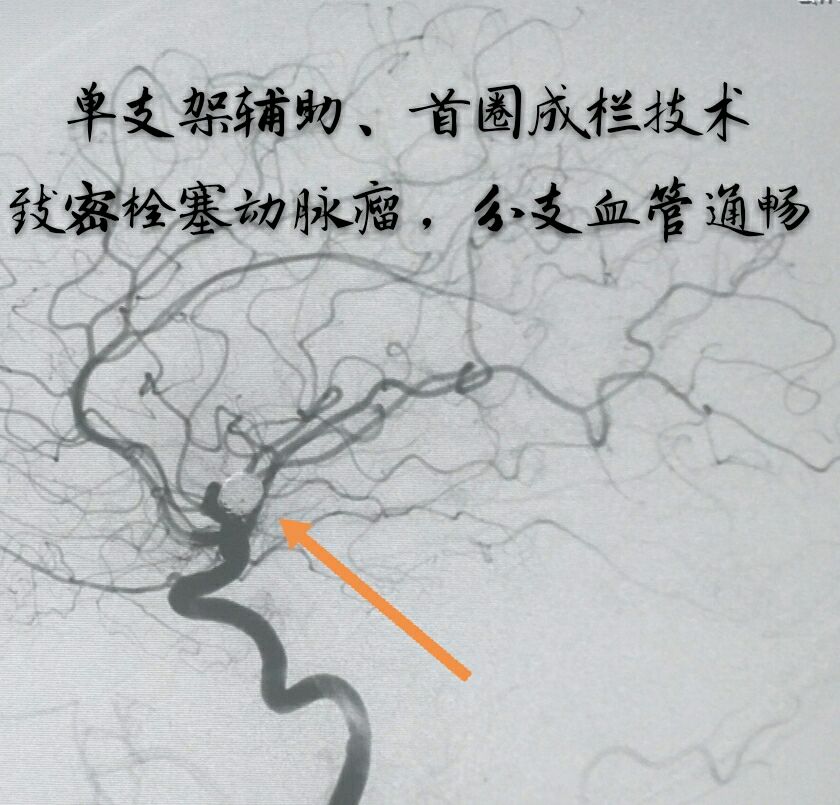

病例十:老年男性患者,间断性头痛1年,DSA示左侧颈内动脉后交通段动脉瘤,后交通动脉从瘤颈部发出

支架打开,首圈完美成栏

最终动脉瘤致密栓塞,载瘤动脉及后交通动脉通畅